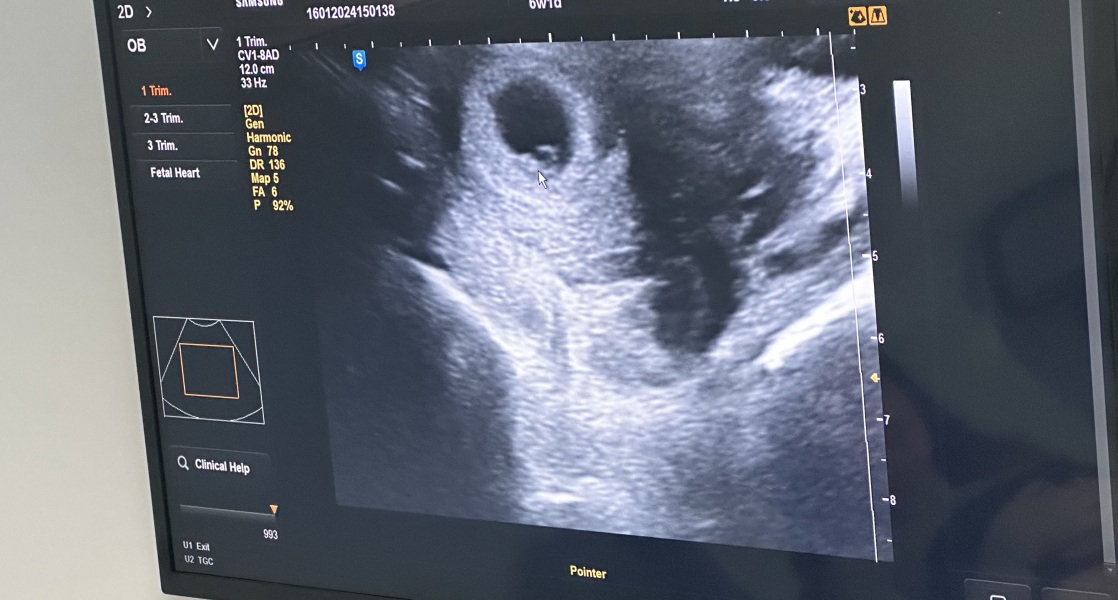

Xur · 16/01/2024 15:22

@VT6 6 weeks and one day , Flo says 2 days but doctor said 1 day.

@Xur fab scan! Pleased your little anchovy is doing great! 😊

Xur · 16/01/2024 17:25

I was given due date of 9th of September.

It was a private scan and it was actually done abroad. We are on holiday. It was pennies to be honest we paid about £40.00 we have another one booked next week, in a posh clinic that will be £80.00.

The Best bit was that these scanners they have here are much newer than the ones I’ve seen in UK. You don’t even need to have full bladder for the early scans. The technology is so sensitive even for the abdominal scan.